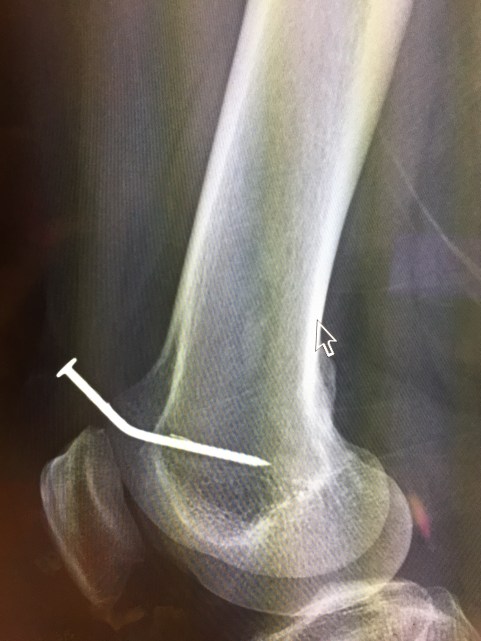

I scribble on the chart, hand him a requisition, and send him to x-ray.

Ten minutes later, we’re looking at the pictures together. “It’s like the gun was right against your leg when it fired.”

I look closer at the picture. “Is that a barb?” I say.

“There are two barbs,” he says. The barbs are tiny hooks on the nail that are meant to keep it from moving. They’re great for decks, and can help them keep their stability for years. They’re not so great for bones.